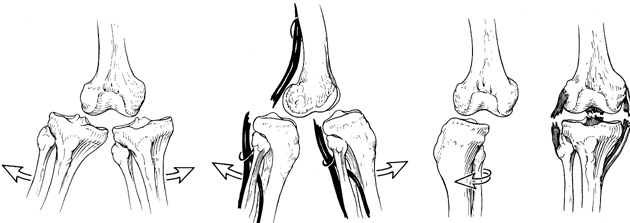

MULTI-LIGAMENT RUPTURE

Although the Anterior Cruciate Ligament is the commonest ligament in the knee to rupture, other ligaments can also be torn, including the medial and lateral collateral ligaments and the posterior cruciate ligament. Reconstruction depends on the pattern of the rupture. In cases of severe trauma, the knee may be dislocated.